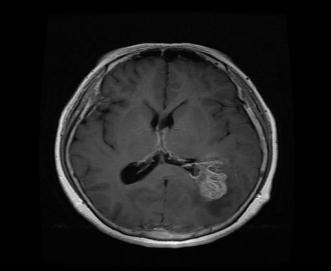

Fig - 1 : Flowchartofproposedmethod TheDatasetofbrainwithtumor: TheDatasetofbrainwithouttumor:

Infirststagewesuccessfullyconvertedtheinputimage(an OpenCV image) to grayscale using edge detection after applying pre-processing. Edge-based segmentation on an imageclassifiespixelsasedgeornon-edgedependingonthe filteroutput.Inregion-basedsegmentation,theimagewas subjected to regional maxima in order to group adjacent pixelswithsimilarvalues.TheCNNmodelwastrainedand testedbeforetheK-meanstechniquewasusedtoidentifythe regionofinterest(ROI),whichwasthenexaminedforthe presenceofatumor.

Fig - 2 : ImagePreprocessing OriginalImage CroppedImage Fig - 3:CNNmodelarchitecture Fig - 4:Trainingmodel